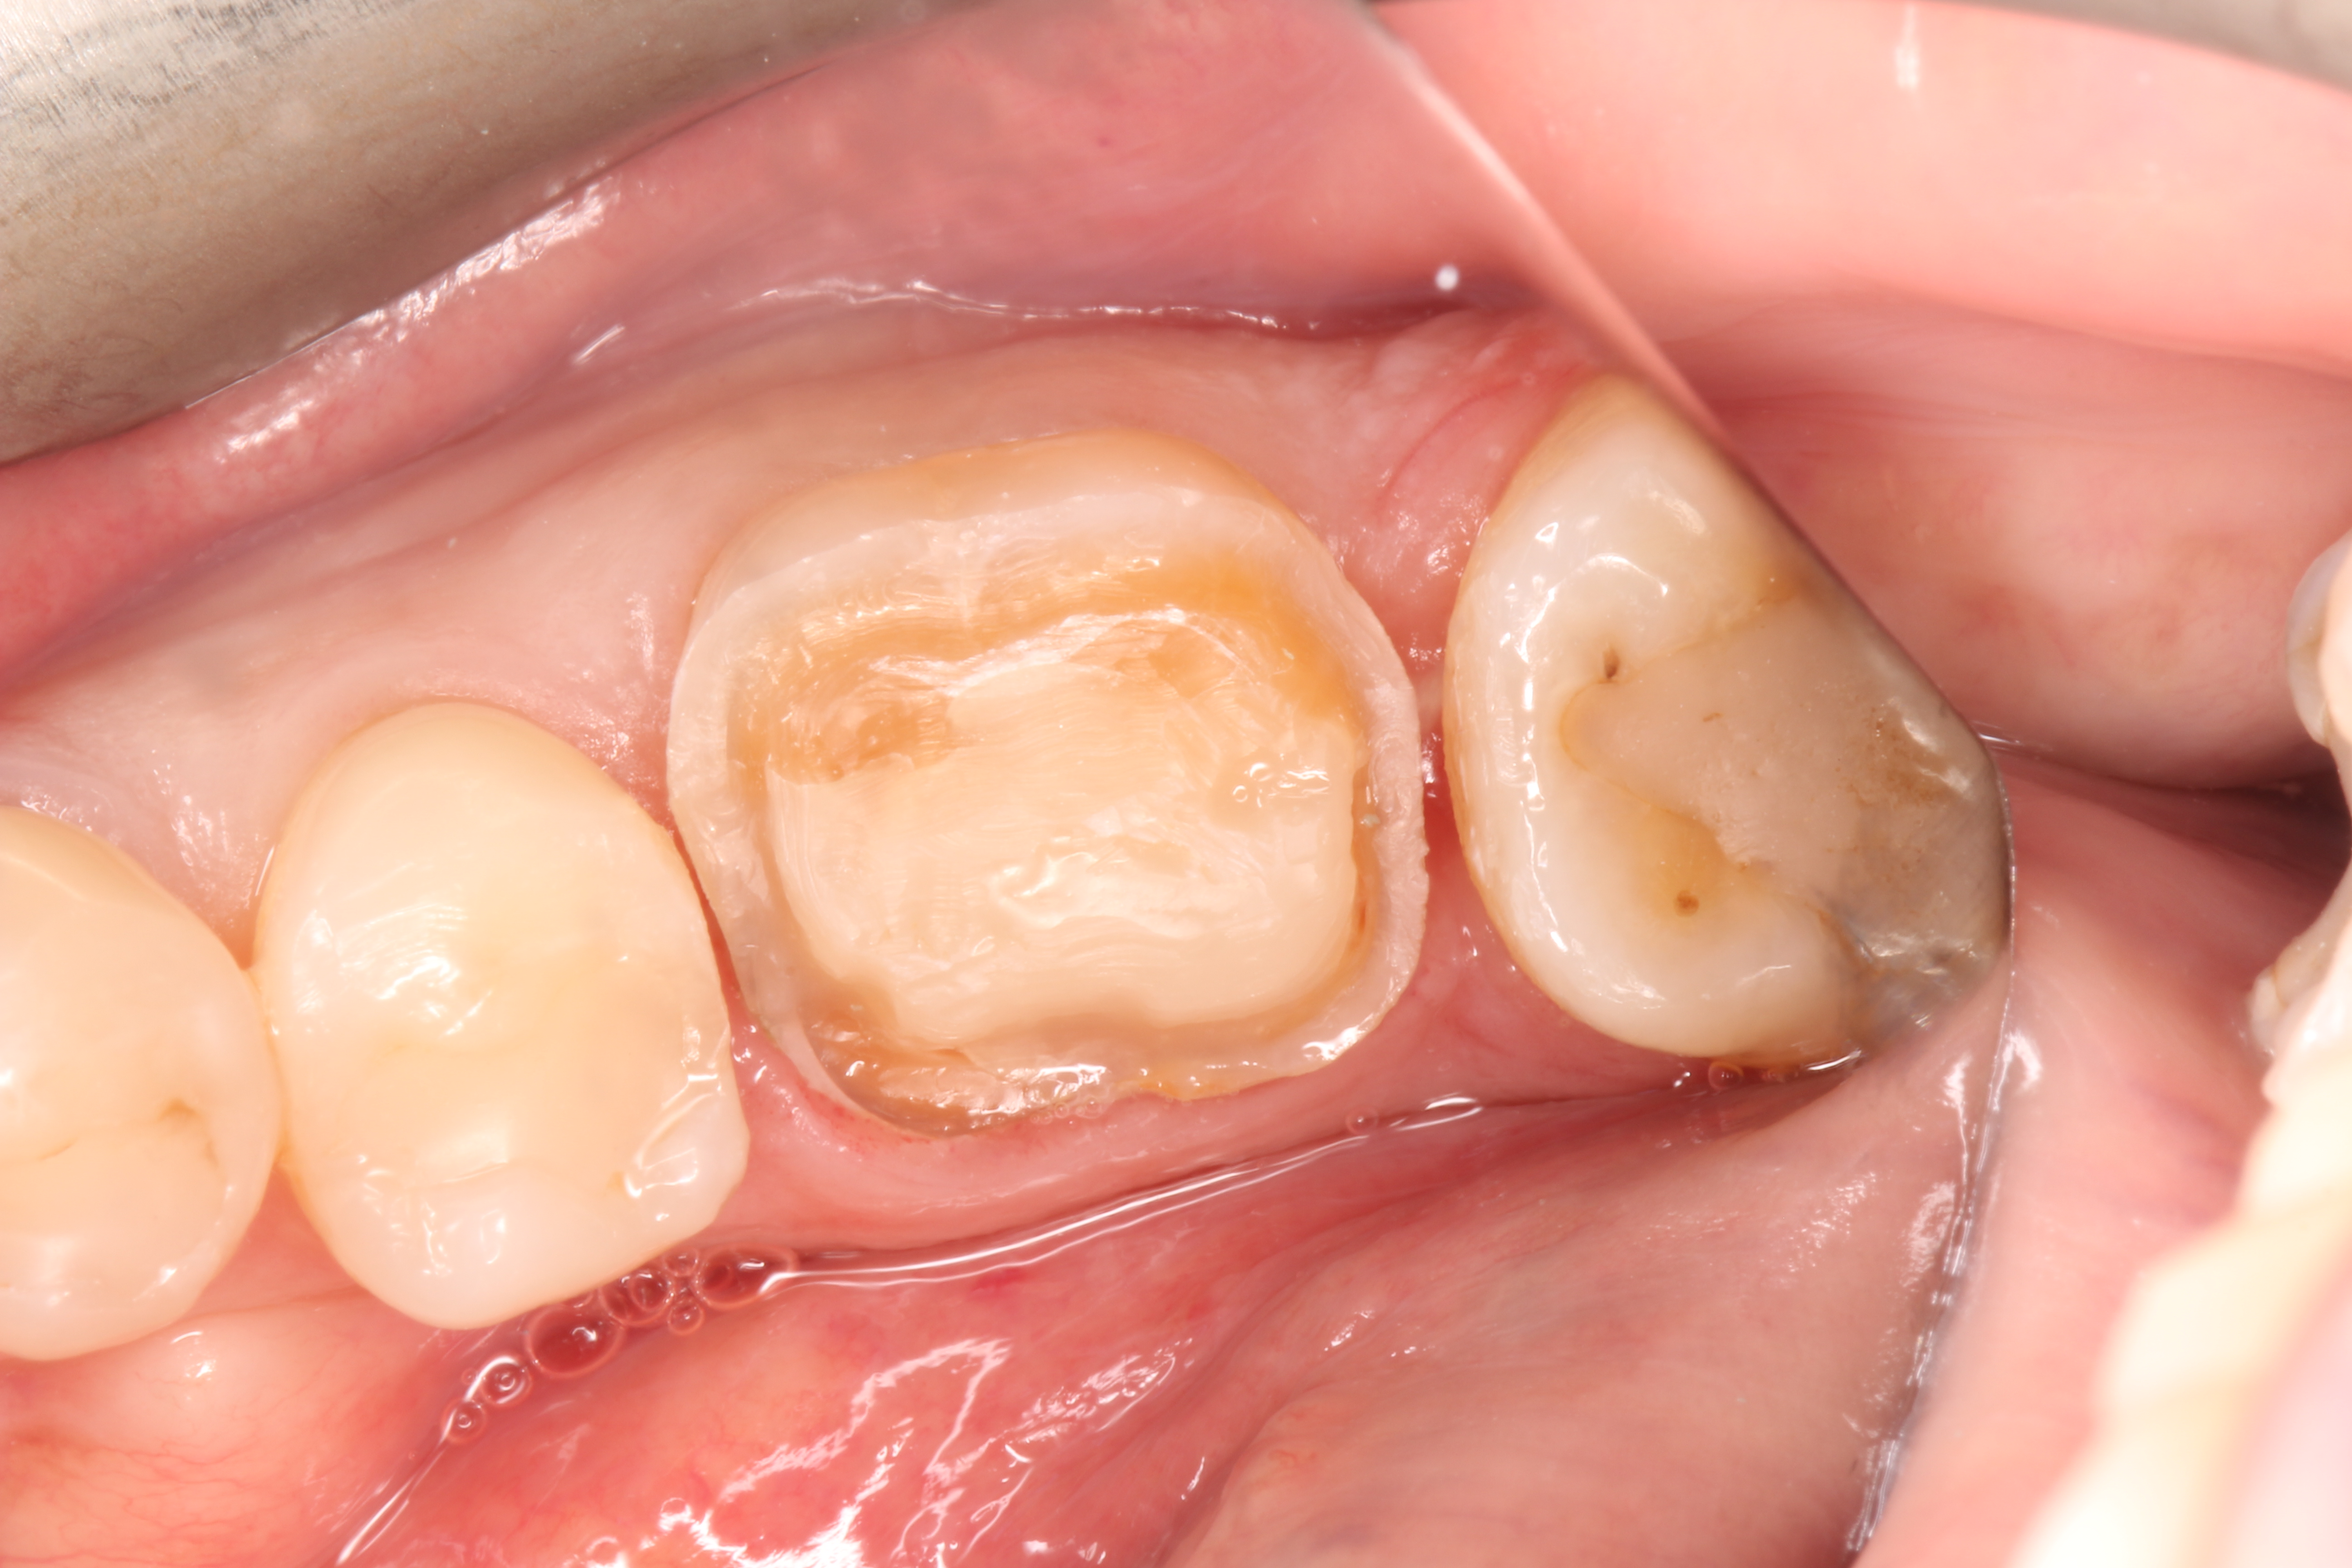

Crowns and onlays by Professor Brian Millar

This course solidified my knowledge and allowed me to practice various cuspal coverage treatments including overlays, onlays and vonlays. I was able to learn about the different preparation techniques and margins required for each indirect material.